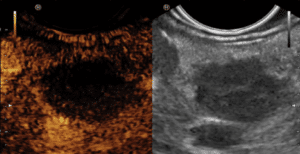

Endosonographie (EUS) Pankreas; 3D-EUS Darstellung von IPMN (intraduktale papilläre mucinöse …